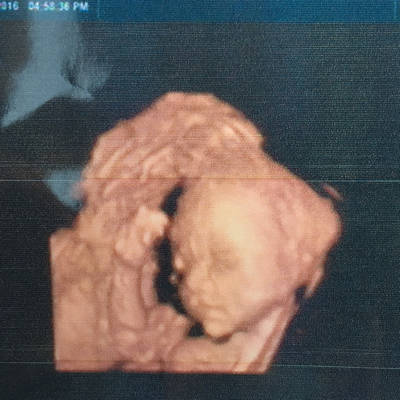

大家帮忙看一下是兔唇吗?

四维查出胎儿唇裂,为所有孕妈敲响警钟!

胎儿双侧唇裂四维成像图